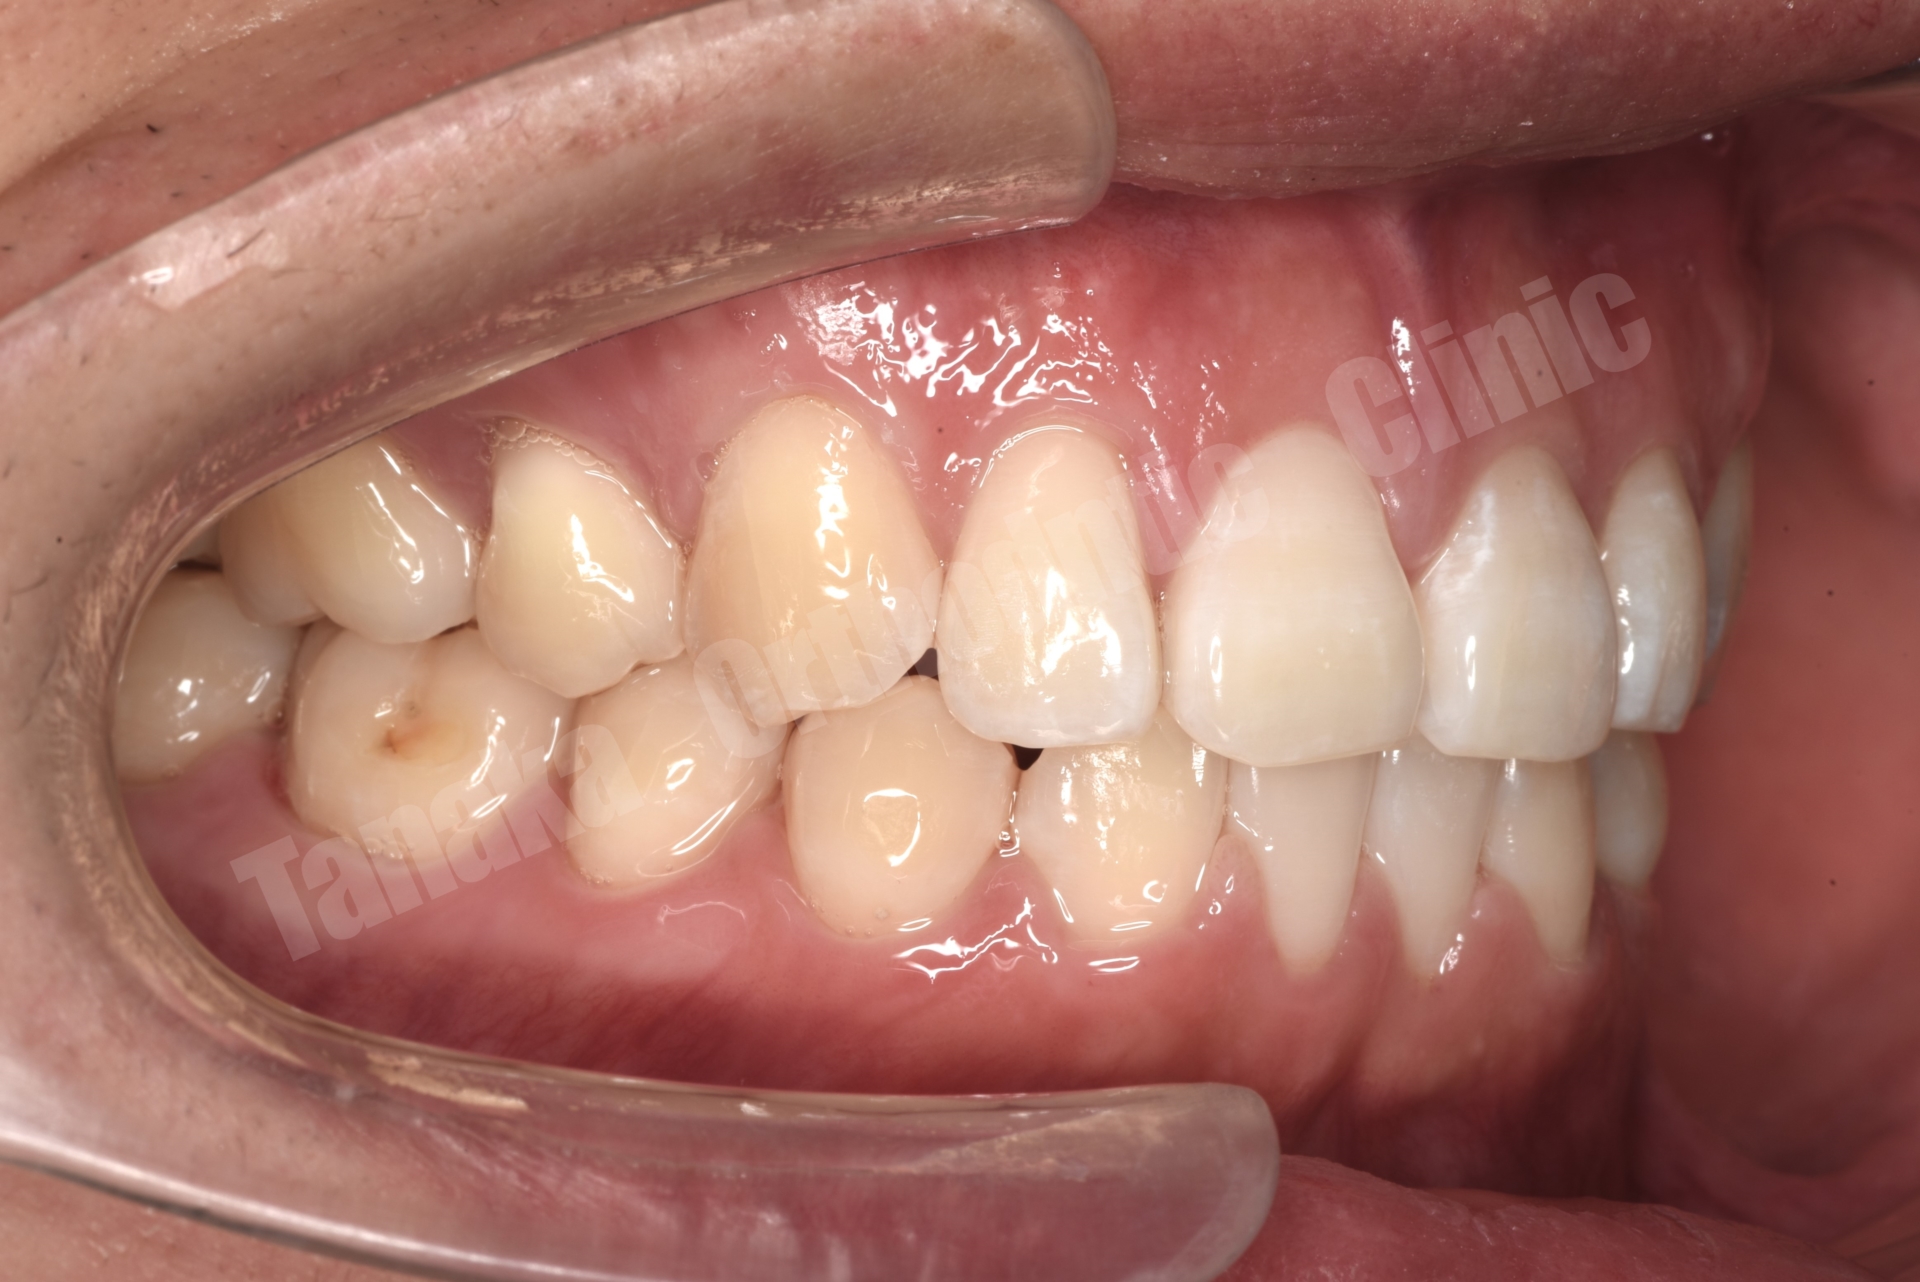

【治療後】

| 診断 | 下顎前歯の先天欠如(2本)によるスペースドアーチ、上顎前歯の唇側傾斜、前歯部水平被蓋が大きい、上顎前歯部叢生、両側AngleⅡ級、上下顎両側8番の埋伏歯、全体的に歯根が短い |

| 抜歯/非抜歯 部位 | 抜歯 上顎両側4番 |

| 治療装置 | マウスピース型矯正装置(インビザライン) 顎間ゴム |